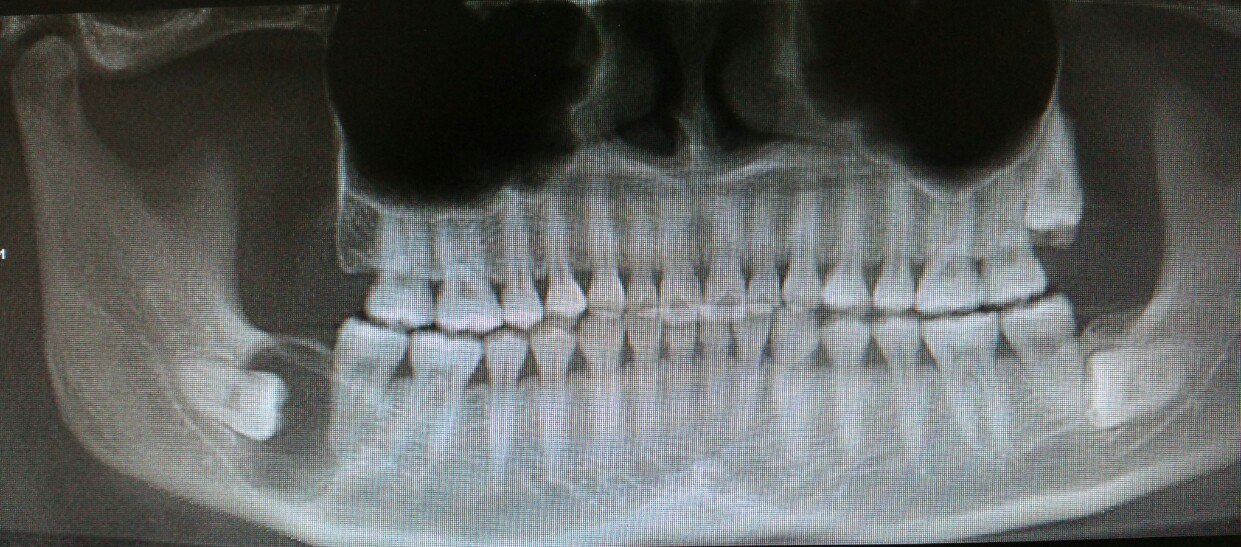

含牙囊肿 一颗爱吹牛的智齿 最后把自己吹飞了 含牙囊肿 含牙囊肿疾病介绍

含牙囊肿dentigerous Cyst 影像ppt

颌骨含牙囊肿图片 搜狗图片搜索